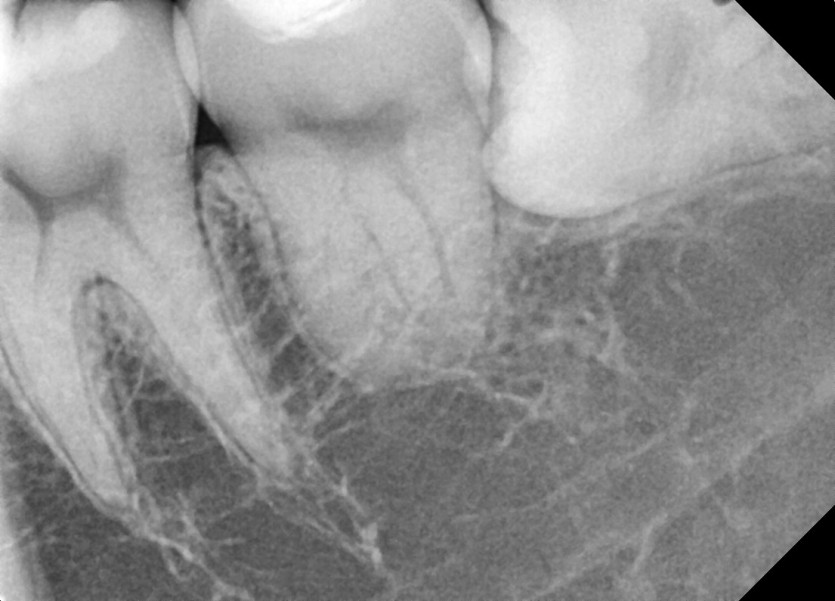

#38,48 사랑니 발치

구강 외과 전문의가 당일 발치했습니다.